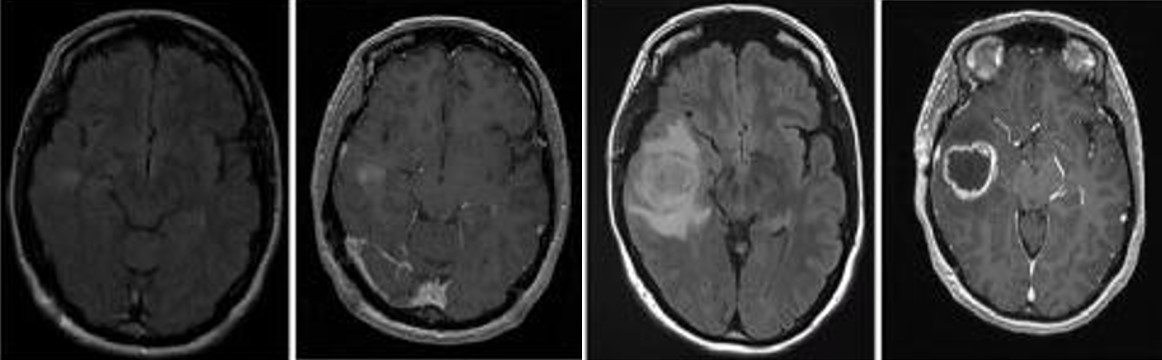

胶质母细胞瘤(Glioblastoma , GBM)是中枢神经系统中比较常见的神经上皮肿瘤,是恶性程度最高的原发性脑肿瘤也是最致命的实体瘤,被世界卫生组织归类为Ⅳ级胶质瘤。GBM 预后差,被诊断后的平均中位生存期为 14个月,其5年生存率为 5%。尽管目前在外科手术,放化疗等医学治疗手段取得了不错的进展,但在延长患者的生存期上仍未取得突破。因此,目前迫切需要筛选鉴定出有效的GBM生物标记物,探索GBM的治疗靶标并解析GBM的发病机理,为GBM的早期诊断及预后评估提供新策略以延缓患者的生存期。

研究表明表皮生长因子受体(EGFR)GBM最常见的基因改变,EGFR的激活与GBM细胞的生长和侵袭密切相关。根据现有统计数据,57% 的原发性 GBM 患者存在 EGFR 突变或异常扩增。作为驱动 GBM病理生理学的信号级联失调的初始上游触发因素,因此EGFR是治疗GBM患者最热门的治疗靶点。

崔红娟教授团队就GBM标志物的筛查、鉴定以及如何管控EGFR在GBM的表达开展了深入研究。首先, GBM患者组织的免疫组化病理检测以及生物信息学分析发现一种能够参与异染色质形成的H3组蛋白甲基化阅读器CBX3(Chromobox 3)在GBM患者中异常高表达,并且与GBM的预后和恶性分级密切相关。功能检测表明了CBX3 在体外和体内显著促进 GBM 细胞的增殖、侵袭和肿瘤发生。从机制上来说,我们通过Ch-IP和Co-IP等一系列生物技术实验证明了CBX3促进GBM 的恶性进展是EGFR 依赖性的,并且进一步揭示了GBM患者发病机理的一条全新的信号通路CBX3-PARK2/STUB1-EGFR。该研究不仅丰富了GBM表观遗传学的研究,也为该信号通路作为GBM潜在治疗靶点的可行性提供了坚实的依据。西南大学2020级博士研究生彭文为第一作者,崔红娟教授为该论文的通讯作者。该研究得到了重庆市自然科学基金和重庆市博士生科研创新项目的支持。